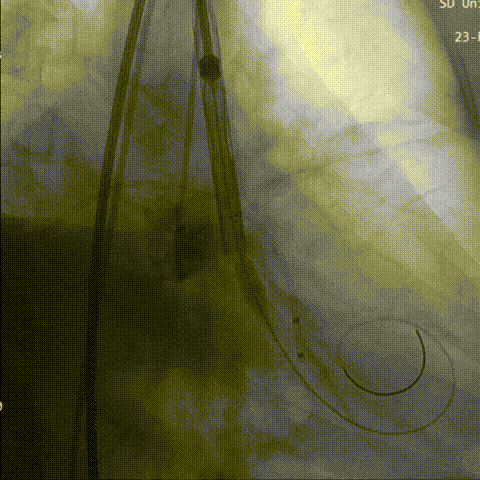

行成功跨瓣后,术者团队用23mm球囊预扩,结合瓣环及球囊预扩情况,植入预装AV26型号瓣膜。

球 囊 预 扩

初始定位

术者结合DSA影像,多角度观察瓣膜情况,在瓣膜达到一个稳定位置后,缓慢释放到工作位,造影评估显示反流明显,行第一次回收。

工作位评估

第一次回收